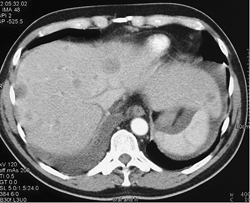

Hepatic Hot Spots Due to SVC Occlusion